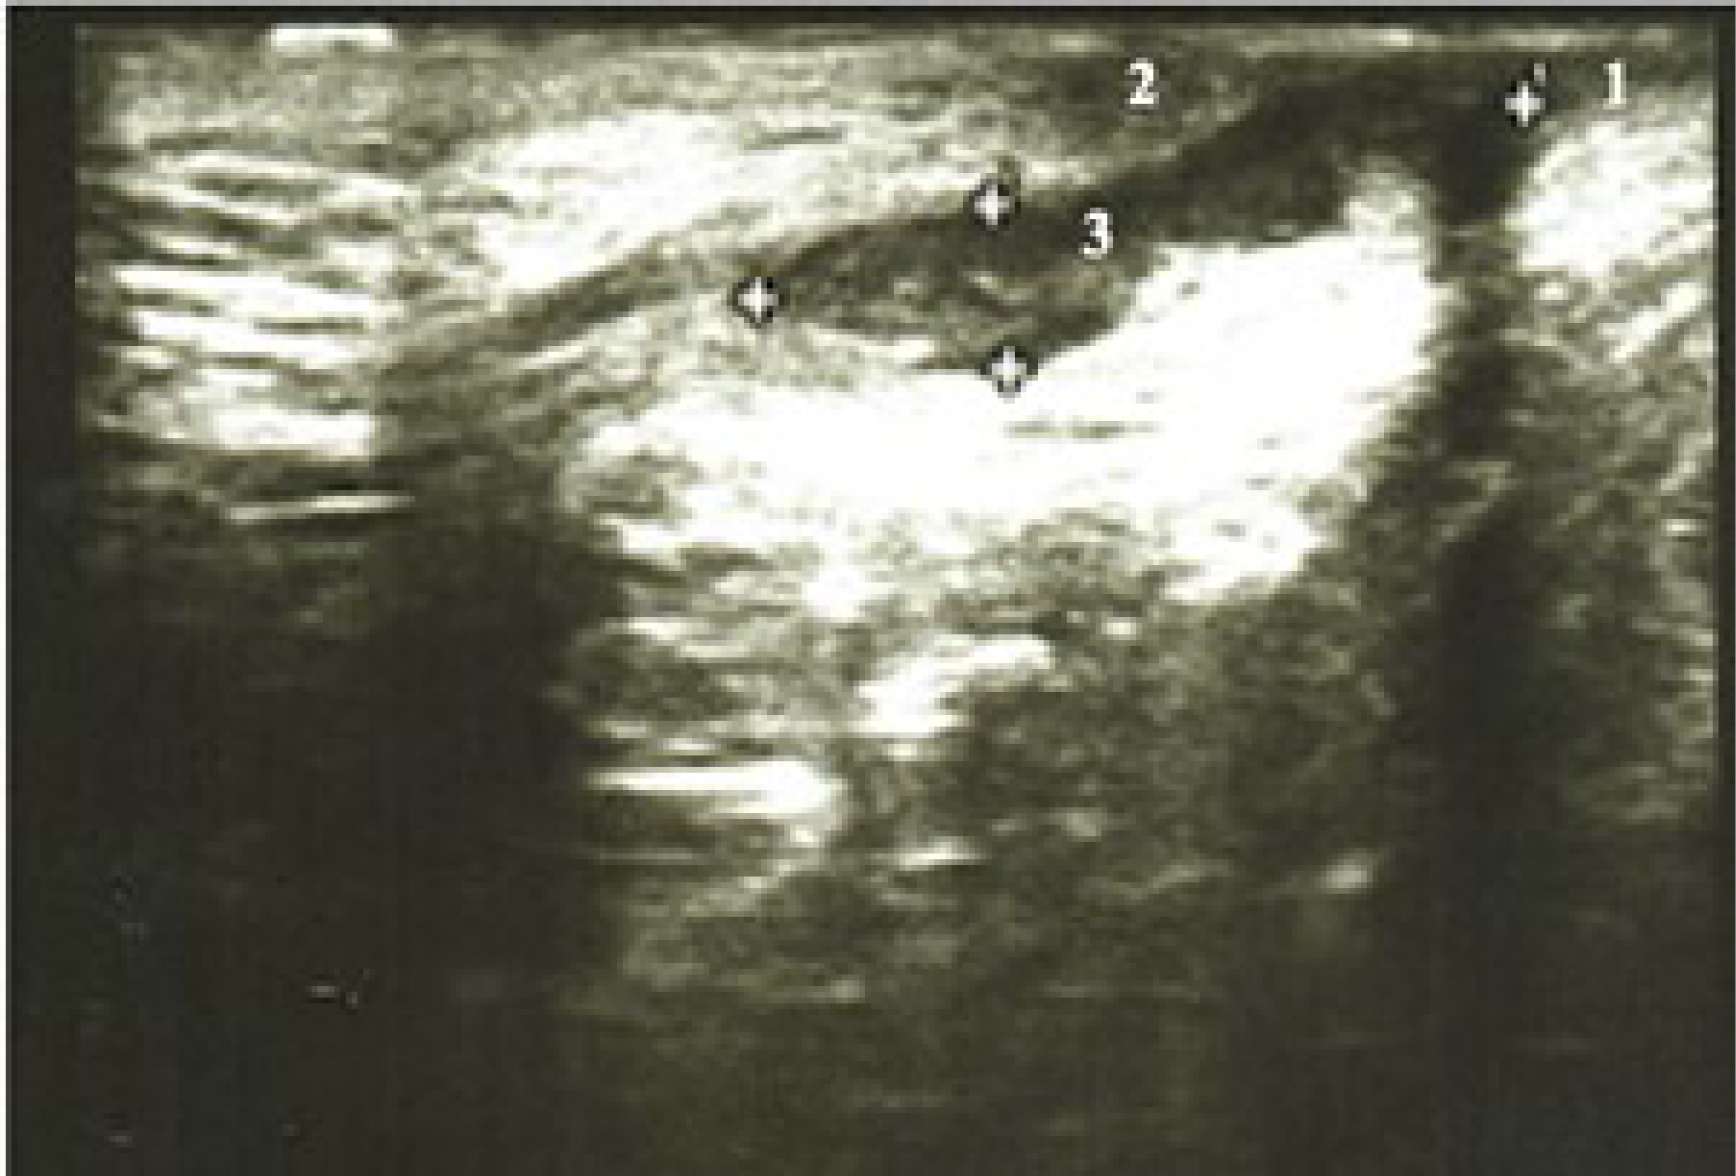

При ультразвуковом исследовании свищ заднего прохода визуализировался как ги-поэхогенная структура линейной формы. Основной свищевой ход обычно имел плотную фиброзную стенку и жидкостное содержимое в просвете свищевого хода, характерное для данного состояния. Еще одним важным моментом является то, что жидкостное содержимое свищевого хода обычно анэхогенно по отношению к окружающим тканям. На стадии воспалительного процесса можно наблюдать изменение эхогенности, в зависимости от состава жидкости и других факторов (рис. 2). Наличие свища заднего прохода подтверждено УЗИ у 12 (13,6%) больных второй группы. При диагностике типа свищевого хода отмечено расхождение данных, полученных при проведении УЗИ и интраоперационной находки в 3 наблюдениях (3,4%).

Рис. 2. Пациент В., 43 лет. Эхограмма заднего транссфинктерного свища заднего прохода, захватывающего более 30% сфинктера. 1 – внутренний сфинктер, 2 – наружный сфинктер, 3 – свищевой ход.

Fig. 2. Patient V., 43 years old. An echogram of the posterior complex transsphincteric fistula. 1 – musculus sphincter ani internus, 2 – musculus sphincter ani externus, 3 – fistula.

По данным УЗИ транссфинктерный свищ заднего прохода с захватом более 30% сфинктера был выявлен у 8 (9,1%) больных, экстрасфинктерный свищ – у 4 (4,5%) пациентов. При проведении оперативного вмешательства и ревизии установлено, что транссфинктерный свищ заднего прохода, захватывающий более 30% сфинктера, обнаружен у 5 (5,4%) пациентов, экстрасфинктерный свищ – у 7 (8,0%) больных.

Транссфинктерный свищ с захватом более 30% замыкательного аппарата прямой кишки был расценен как экстрасфинктерный свищ в 3 (3,4%) наблюдениях.